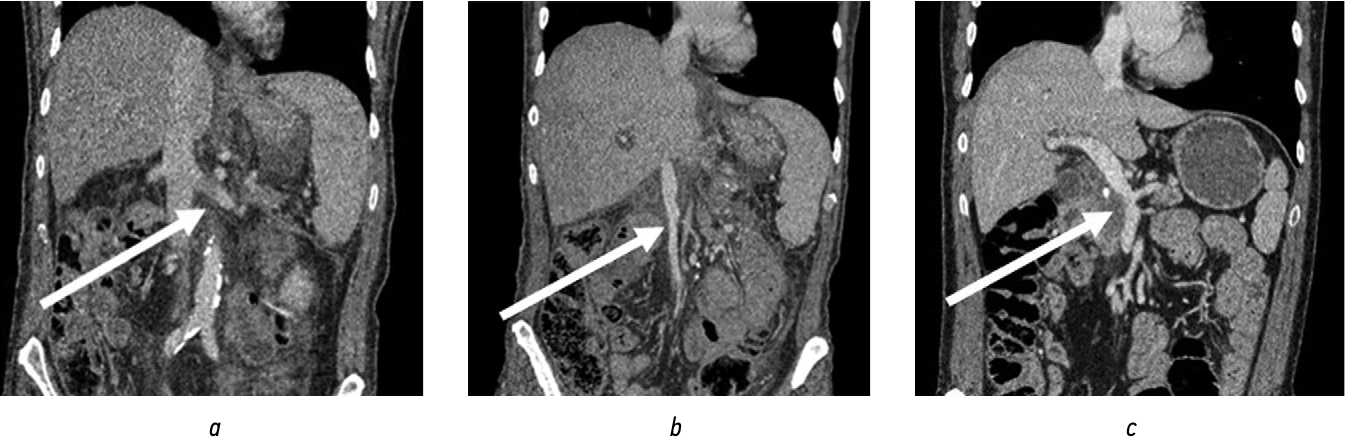

Предоперационная оценка вариантов поражения мезентерико-портального сегмента по результатам КТ-ангиографии (рис. 1) позволяла спланировать после выполнения ГПДР адекватный вариант сосудистой реконструкции.

Рис. 1. Компьютерно-томографическая ангиография: a — опухоль головки поджелудочной железы с инвазией конфлюенса и стенки воротной вены; b — мезентерико-портальный анастомоз «конец-в-конец» после резекции конфлюенса воротной вены; c — дистальный сплено-ренальный анастомоз «конец-в-бок» / Fig. 1. Сomputed tomographic angiography: a — pancreatic head tumor with confluence invasion and portal vein wall; b — mesenteric-portal "end-to-end" anastomosis after resection of portal vein confluence; c — distal "end-to-side" splan-renal anastomosis

В настоящее время КТ-ангиография является «золотым стандартом» диагностики протоковой аденокарциномы поджелудочной железы, поскольку позволяет не только диагностировать опухоль, но и оценить ее распространенность и резектабельность. В сравнении с интраоперационными данными КТ-ангиография демонстрирует высокую точность в выявлении вариантов артериальной и венозной ангиоархитектоники, гемодинамически значимых стенозов и обструкций, что существенно влияет на выбор оперативного вмешательства [13, 14].